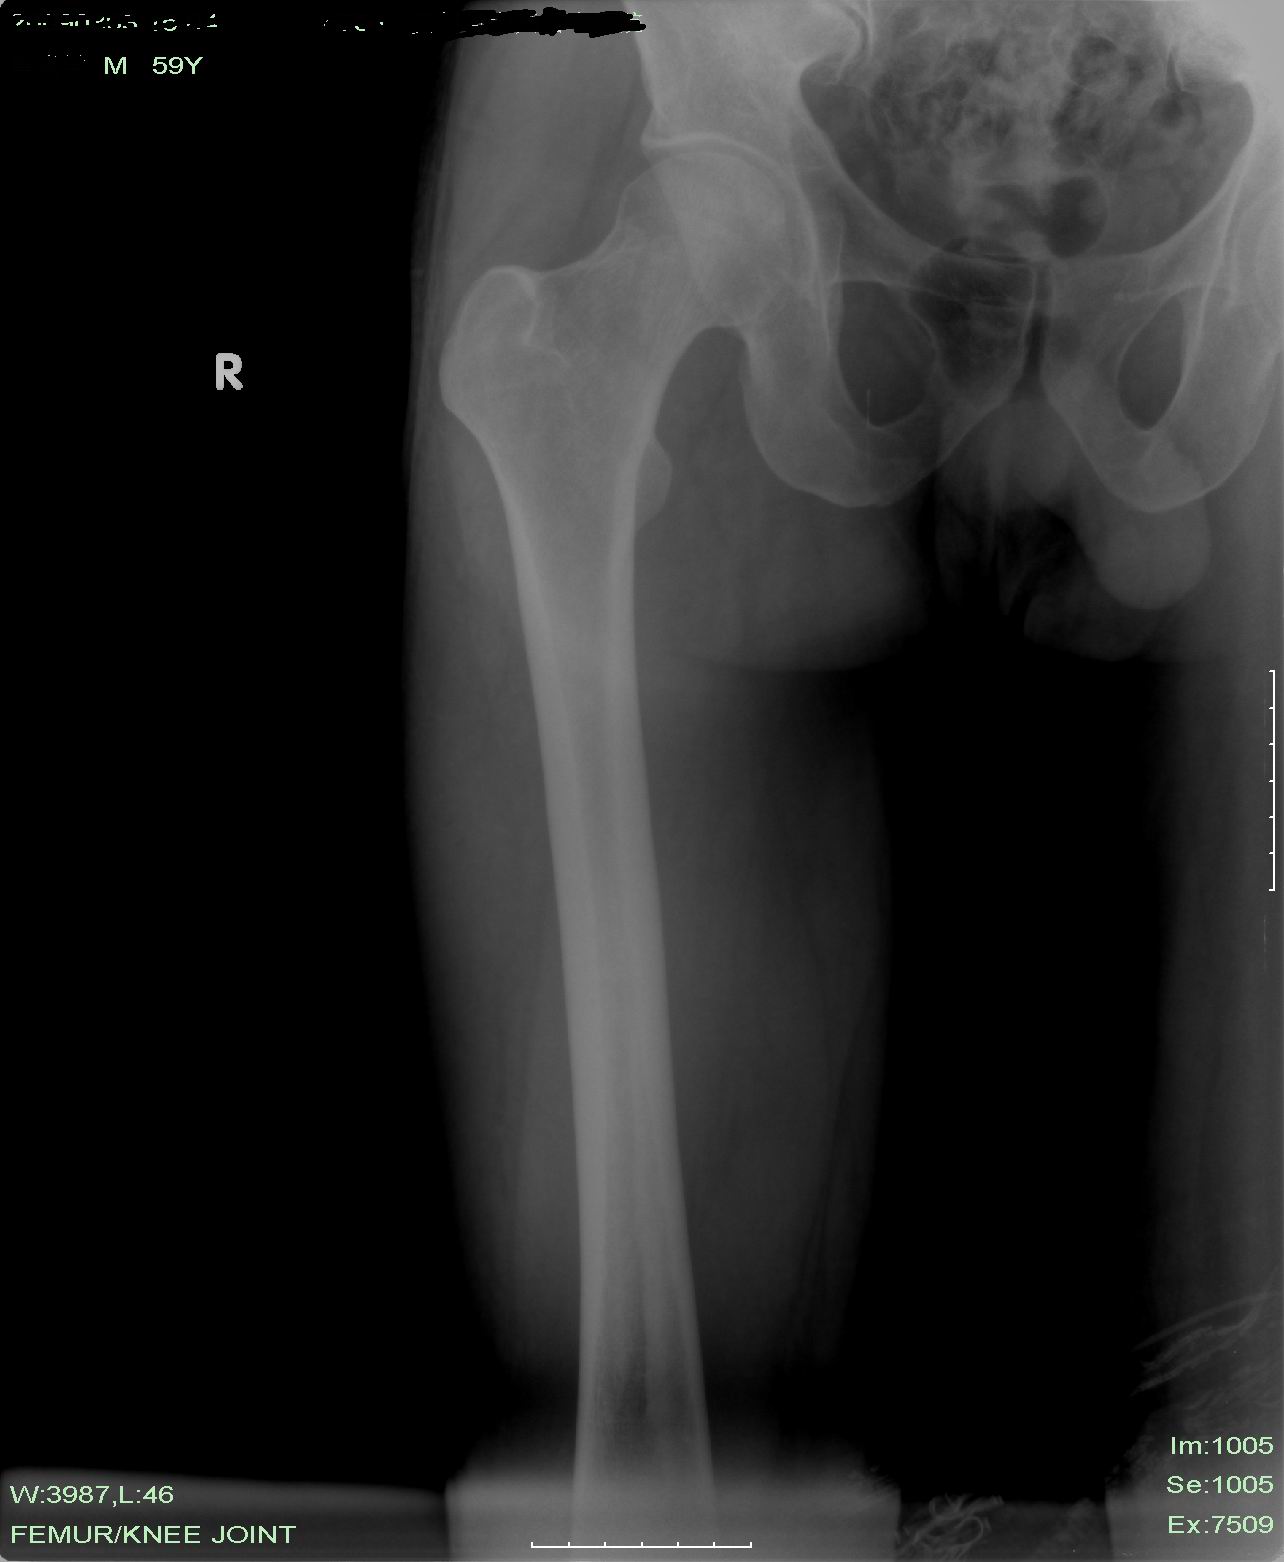

标题: X5404:右大腿突发疼痛3天,查无特殊。我看没什么问题,临 [打印本页]

标题: X5404:右大腿突发疼痛3天,查无特殊。我看没什么问题,临

临床的说有问题是对的,因为患者右大腿疼痛。我们平片所及的没见有问题,此问题该临床开动脑筋继续找。

应该是平片未见异常;临床说有问题是因为病人有疼痛,可进一步检查。

x片未见明显异常,做进一步检查和考虑软组织病变~